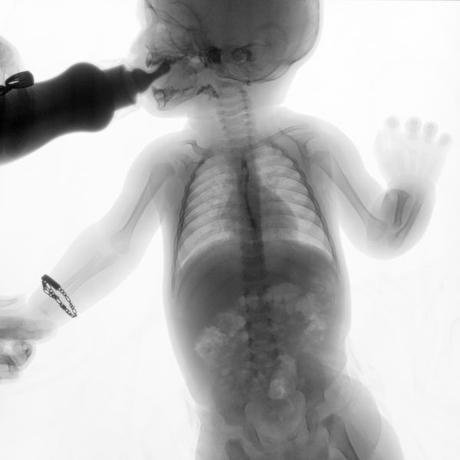

ESTUDIO SOLICITADO: SERIE ESOFAGOGASTRODUODENAL.

Se realiza Esofagograma con material de contraste baritado, por vía oral y por medio de control fluoroscópico se toman distintas proyecciones observando lo siguiente.

Se observa mecánica de la deglución con adecuado paso de medio de contraste de faringe a esófago sin presencia de defectos de llenado depósitos anómalos o fuga del mismo.

ESÓFAGO se observa de situación, calibre y trayecto normal. Contornos regulares y bien definidos. No se observan depósitos anómalos, defectos de llenado o fuga del medio de contraste.

UNION ESOFAGOGASTRICA se observa con calibre y situación normal. Sin observar reflujo a las maniobras de valsalva

ESTOMAGO se observa en su situación habitual, distendido, sin defectos de llenado.

- Actualmente no se demuestra Reflujo gastro-esofágico.

- Estudio de apariencia normal.